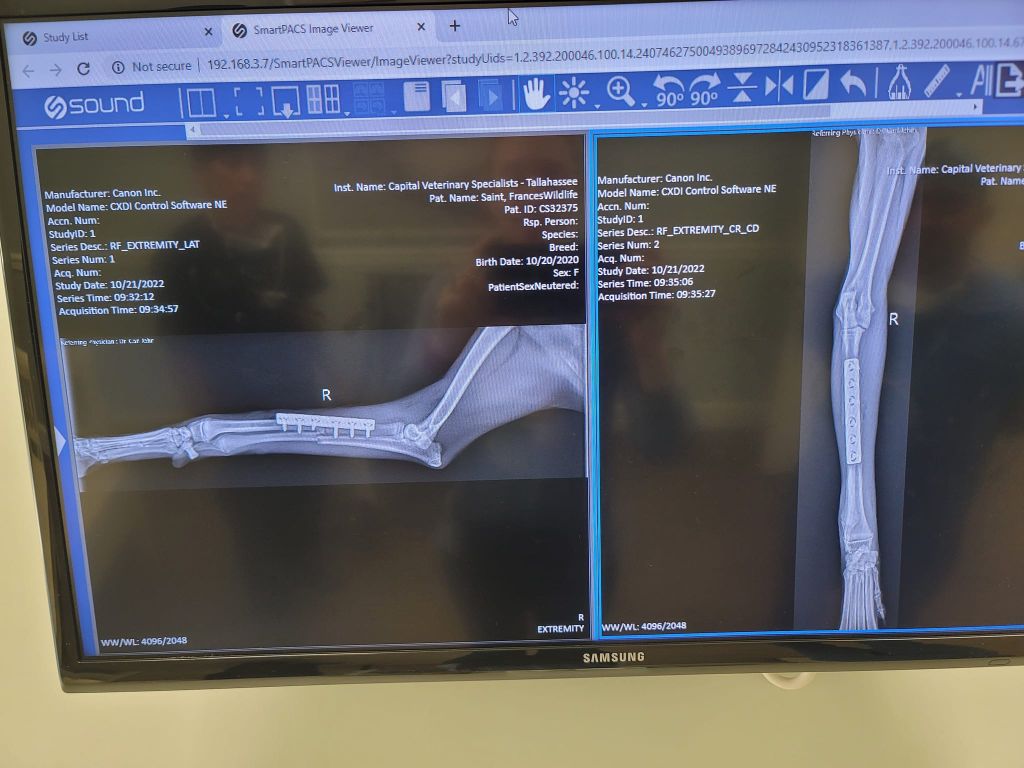

Veterinary Technician Shaun Hall at Allied Veterinary Hospital assists while the leg is splinted.

Rescuers told The Miami Herald that the animal was rescued just in time and had suffered fractures to her right front radius and ulna.

Veterinary Technician Shaun Hall at Allied Veterinary Hospital assists while the leg is splinted.

The female coyote had surgery to repair broken bones but is expected to make a full recovery.

The female coyote had surgery to repair broken bones but is expected to make a full recovery.